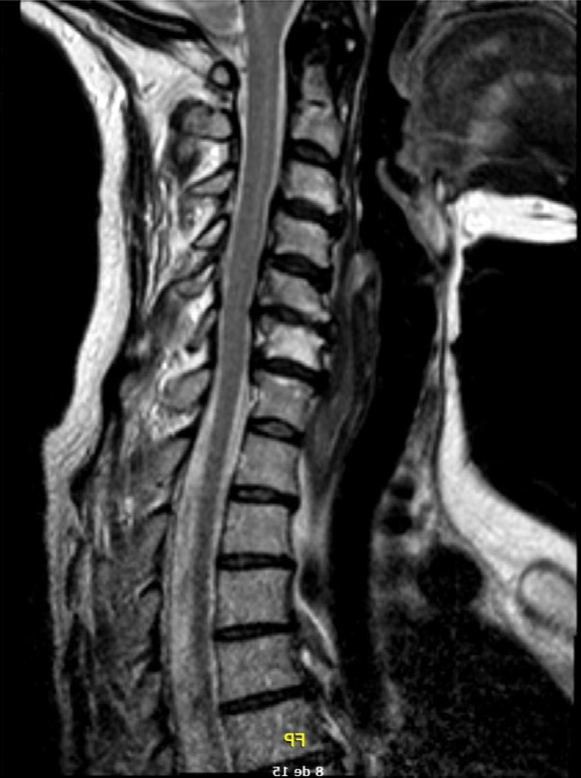

- RMN: discopatía cervical grave C4-C7, especialmente crítica en C5-C6 sin alteraciones de señal medular.

Degeneración cuerpo C5 con discopatía cervical C4-C7 grave.